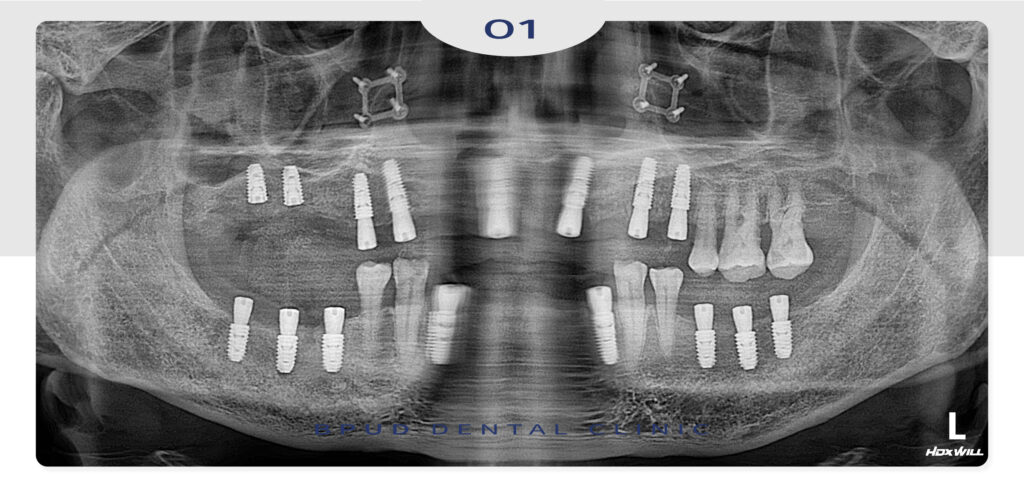

오늘은 오랜 기간 거의 무치악 상태로

생활하시다가 위, 아래 부평전체임플란트를

진행하신 환자분을 소개해 드리려고 합니다.

환자분께서는 지인 분의 소개로 내원해 주셨는데

사진에서 보는 것과 같이 전반적으로 치아를

상실하신 상태였고 더불어 남아 있는 치아마저

예후가 좋지 않아 발치가 필요한 상황이었는데요.

따라서 치아 상실 부위와 예후가 불량한 치아들을

발치한 후 임플란트 식립과 뼈이식을 진행하기로

계획하였습니다.